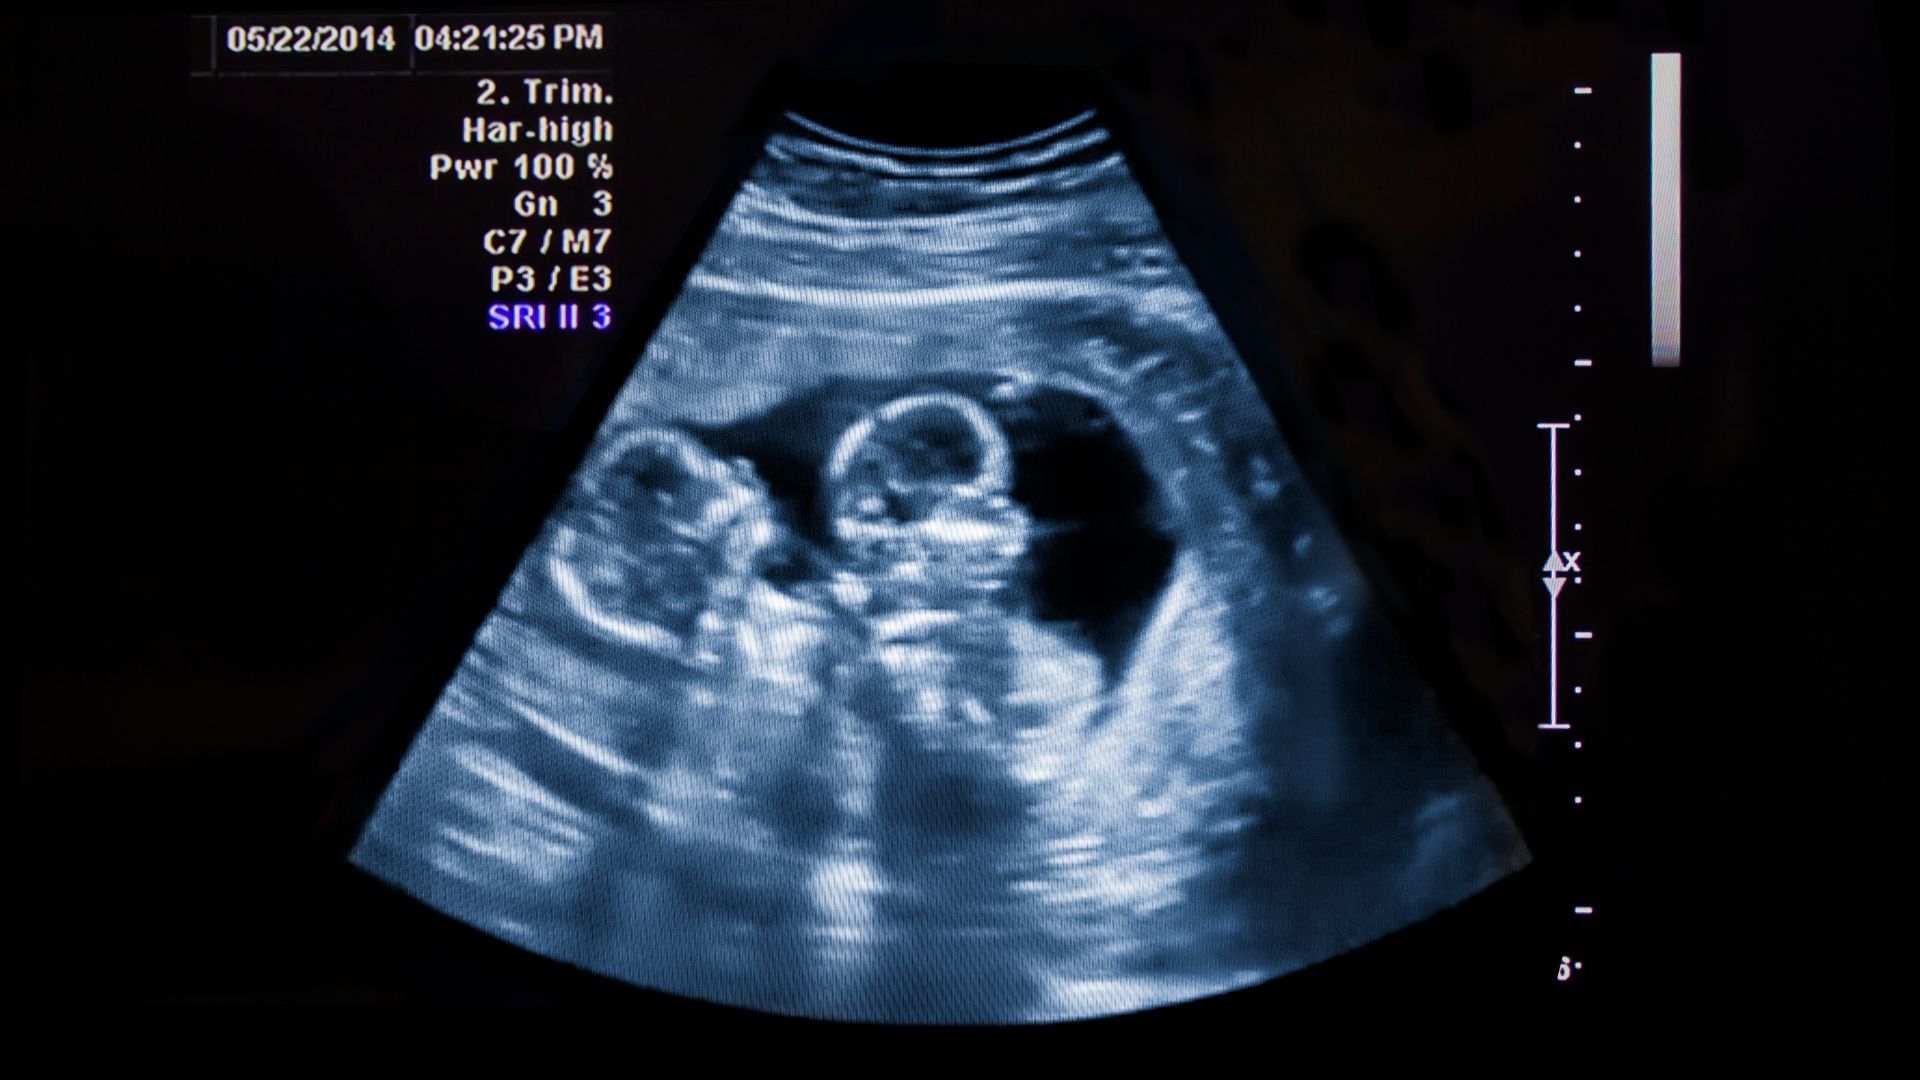

Saya masih ingat betul hari pertama saat mengetahui sedang hamil kembar. Hari yang awalnya saya kira akan berjalan biasa saja, kontrol kehamilan, duduk di ruang tunggu, mengisi formulir, lalu pulang sambil mikir mau makan apa. Tapi ternyata semesta punya rencana lain. Dokter memeriksa hasil USG, diam sebentar, lalu berkata dengan nada setengah kaget. “Bu, ini ada dua janin.”

Kembar identik terjadi ketika satu sel telur dibuahi oleh satu sperma, lalu sel telur tersebut membelah menjadi dua embrio. Karena berasal dari satu sumber yang sama, kembar identik pastilah memiliki DNA yang sama, biasanya wajah sangat mirip, jenis kelaminnya sama.

Kemungkinan terjadinya kembar identik sekitar 3–5 dari 1.000 kelahiran. Angka ini relatif sama di berbagai belahan dunia, dan sampai sekarang, proses terjadinya kembar identik masih dianggap acak. Artinya, kembar identik tidak terbukti kuat diturunkan dalam keluarga.

2. Kembar Non-Identik (Dizigot / Fraternal)

Nah, ini jenis kembar yang sering dikaitkan dengan “turunan” dalam keluarga. Kembar non-identik terjadi ketika dua sel telur dilepaskan dan dibuahi oleh dua sperma yang berbeda dalam satu siklus kehamilan. Hasilnya bisa beda wajah, bisa beda kepribadian, bisa beda jenis kelamin. Secara genetik seperti kakak-adik biasa, hanya saja lahir bersamaan.

Kedua anak kembar saya termasuk kategori ini. Wajah mereka tidak mirip, karakternya pun jauh berbeda. Yang satu kalem, yang satu aktif. Yang satu hobi makan, yang satu picky. Kalau tidak lahir di hari yang sama, mungkin orang tak akan menyangka mereka kembar.